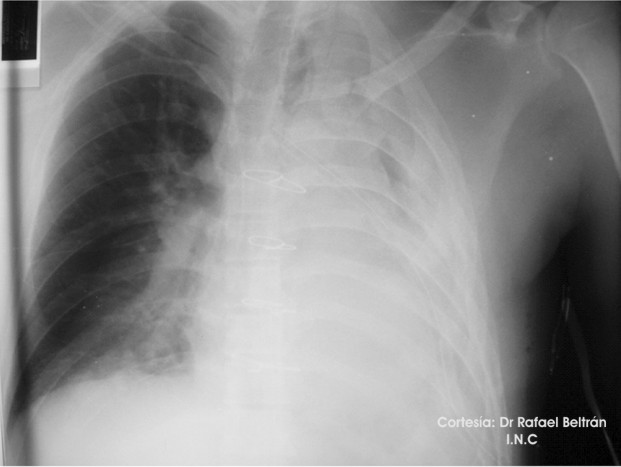

Rx Torax de control (POP inmediato) No muestra complicaciones POP.Podemos ver la posicion correcta del cateter central subclavio derecho (debió colocarse izquierdo pero debido al tipo de abordaje y al riesgo de lesión subclavia izquierda, en común acuerdo con el equipo quirúrgico, se escogió la vena subclavia derecho )